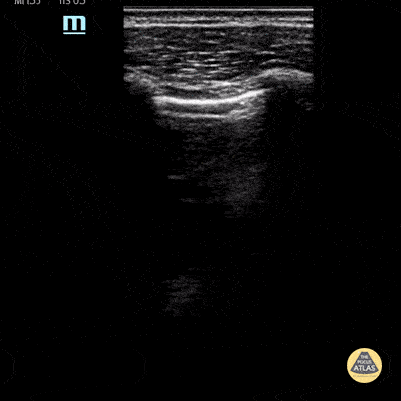

Lung point indicative of pneumothorax. Contributor: Peter Gutierrez, MD, FAAP, Emory University School of Medicine/Children's Healthcare of Atlanta, @pocuspete